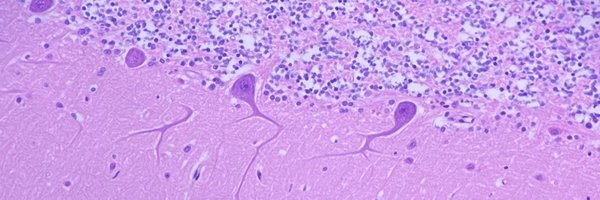

This might LOOK like a pilocytic astrocytoma, but it's actually piloid gliosis adjacent to an ependymoma. Tricky! #pathology #neuropath #PathTwitter